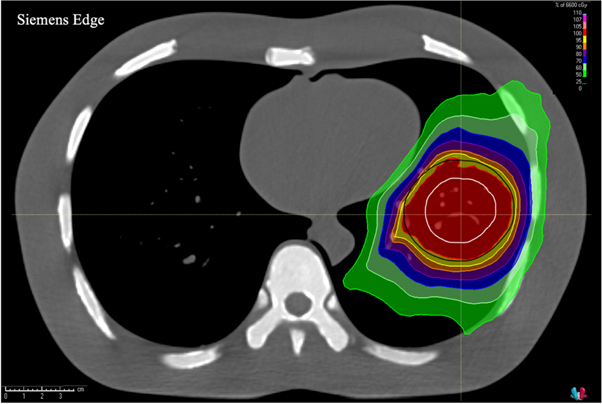

An axial image displaying isodose lines overlaid on the CTV and PTV contours for the dose calculation with the planning CT thorax phantom image set for the large volume treatment plan is shown in figure 3. Figure 4 shows dose-difference maps for axial image slices (corresponding to that seen in figure 3 for the planning CT) for each ClearRT acquisition and calibration mode evaluated in the study. Tables 2 and 3 show relative and absolute differences in selected target volume and OAR DVH metrics used to assess plan quality for ClearRT in comparison to the planning CT. The most clinically relevant DVH parameters compared for the target volumes (CTV and PTV) were the dose to 98% of the volume (D98, near-minimum dose), D95 (related to the prescription dose), Dmean, and D2 (near-maximum dose), while the most relevant parameters compared for the critical structures (OARs) were Dmean and D2. Additionally, figure 5 shows relative differences for all DVH metrics evaluated (including those listed in table 2 as well as D99, D50, and D1) for the target volumes for each of the ClearRT acquisition modes and calibrations assessed in this study.

Figure 3. Axial image of the thorax phantom acquired with the planning CT displaying isodose lines calculated for the large volume treatment plan. The CTV (white) and PTV (black) contours are shown as well.